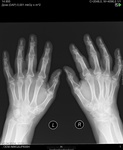

Какую стадию здесь по Штейнброкеру написать?

Штейнброкер - это голова. Может и рискую, но не вижу никакой стадии РА, ни по кому.

Здесь нет РА, извините. А у Штейнброкера нет деления на 2А и 2 Б.

Андрей Юрьевич, maker4ik, а каково ваше мнение: норма?остеоартроз?

Как р-признаки дегенеративных изменений мелких суставов кисти.

Изменения в дистальных межфаланговых суставах могут быть в поздних стадиях ревматоидного артрита - в 3 и 4 стадии по Штейнброкеру. Начиная с 3-й стадии РА должны быть множественные эрозии суставных поверхностей, чего здесь нет. Отвечая на вопрос автора о стадии РА, нужно подумать о второй или первой стадии (по видимому диагноз уже клинический, раз вопрос о диагнозе не стоит).

Теоретически, явные артрозные изменения на снимке могут быть не единственной патологией кистей у данного пациента. Ну и далее как обычно - пол, возраст, профмаршрут и вся клиническая история заболевания + лабораторные данные.

Я не стадирую РА по стадиям, потому автору и не ответил, он ведь стадию точную спрашивал. А описываю найденные изменения. Есть околосуставной остеопроз. Узуры в головках пястных не я на снимок принёс.)

Покажите стрелочками, пожалуйчта, остеопороз и эрозии.

Думал, что все позабыли. Про эрозии, которые не обозначены были. Решил, что все их увидели, как и Никто.) Только я их пока не узнал, кистовидные просветления есть на снимке пока. Да, их много, отметил выборочно, чутка.) Пока не эрозии, но, может, станут потом, когда.) Остеопороз околосуставной - это не моё ноу-хау. Я даже не знаю, как его показать, если Вам его не видать. Уже на уровне ощущений. Снимок цифровой. Есть мягкие ткани на нём, плотность их есть для сравнения. Ободка склероза головок пястных нема, плотность их бумажная. В позитиве было бы показательнее, да. Но есть негатив. С остеопорозом пока что беда.

Т.е. эрозий все же нет? Ощущать остеопороз, конечно, очень хорошо, но только он один (если вдруг есть) не может быть критерием для рентгенологического выставления заключения РА. Потому что вполне божет оказаться, например, постменопаузальным или связанным с приемом лекарственных препаратов.